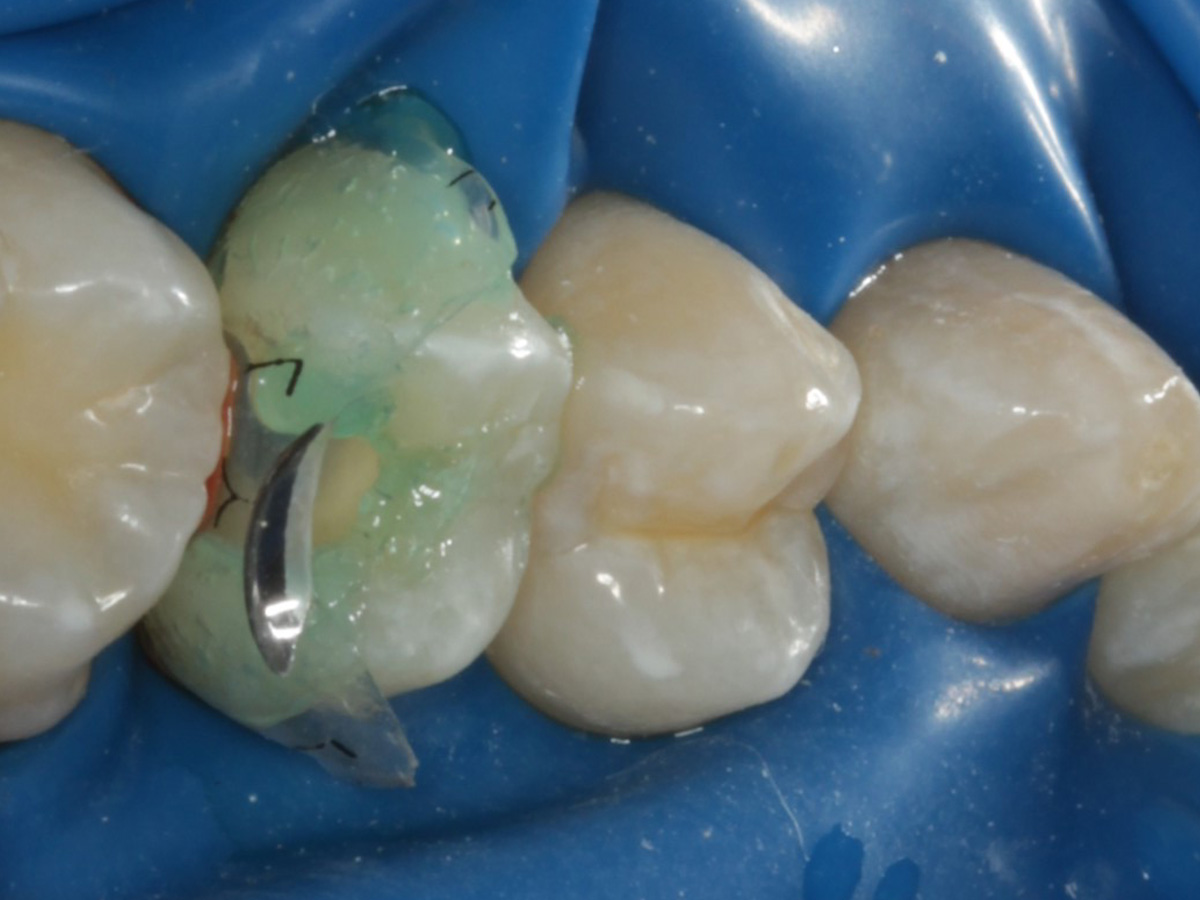

Abbildung 1

Bissflügelröntgenaufnahme, Approximalraumkaries an Zahn 25 distal

Nach Applikation der Matrize: Evolve Schwarz Prämolar- 7 mm; Schmelzätzung

Nach Spray und Trocknung der Kavität: perfekte Adaptation der Matrize insbesondere tief subgingival